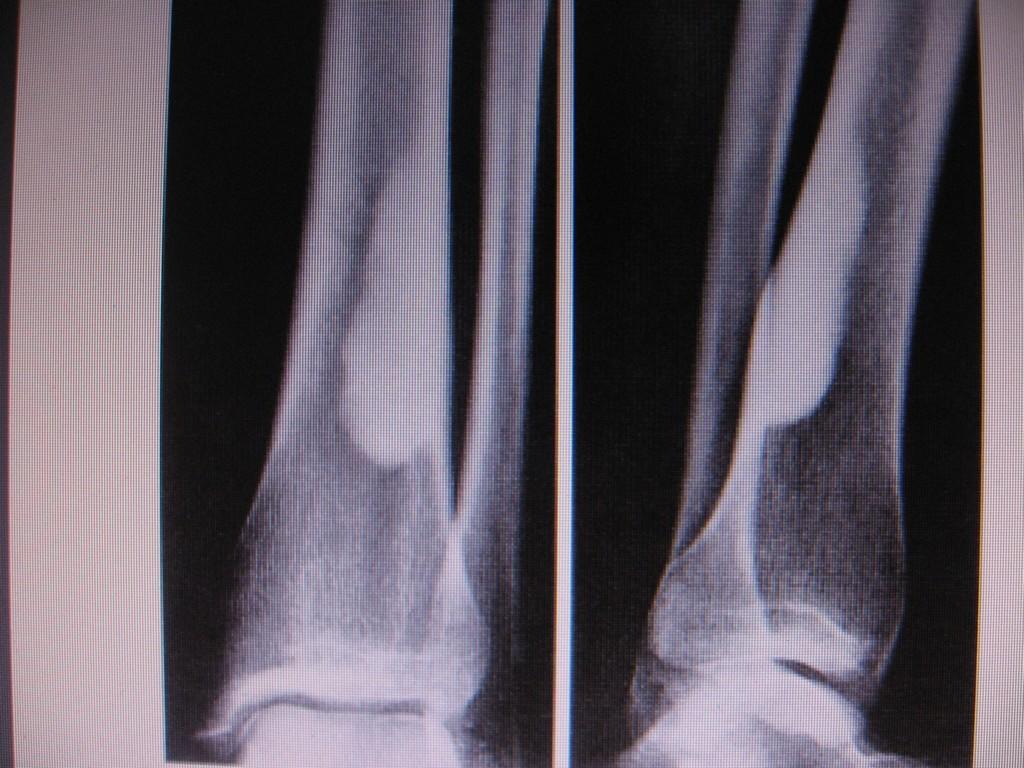

男性,47岁,在一次外伤摄片中发现右胫骨上段条状高密度影,ct横断面上发现条状高密度影(钙化及骨化密度)位于胫骨皮质下,和皮质紧密相连,我考虑纤维性骨皮质缺损钙化可能性大,大家认为呢?大家注意看定位片,高密度病灶是很长的,横断面我只是选取了其中的几个层面。

这是一例经病理证实的纤维性骨皮质缺损钙化病例。

大家注意看定位片,高密度病灶是很长的,横断面我只是选取了其中的几个层面。